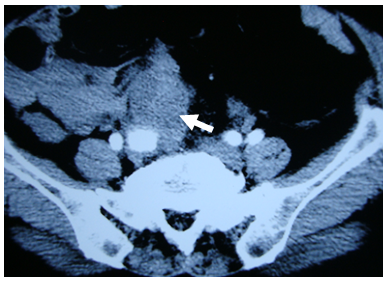

A 66-year-old female presented with a >10-year history of hypertension. She began to experienced dull pain in the lower abdomen and abdominal distension two days prior to admission. When she defecated six hours before admission, the pain suddenly aggravated and gradually spread to the whole abdomen, accompanied by dizziness, nausea, and vomiting, as well as symptoms of shock, including prefuse whole-body sweating and chills in all four limbs. Blood pressure was only 74/59mmHg, she was semilucid with a pained expression, and limbs were wet and cold. Her stomach was distended and felt soft. The whole abdomen was sensitive to applied pressure, particularly the lower abdomen. Abdominal puncture was performed to draw a sample of non-condensable blood. Immediate emergency care included rapid fluid infusion and a blood transfusion. A CT scan revealed an abdominal enhancement consistent with expansion of the right iliac artery and there were masses in the soft tissues adjacent to the common iliac artery. There also appeared to be retroperitoneal hematomas, hence rupture of the aneurysm was suspected (Figure 1). Emergent exploratory laparotomy was performed under general anesthesia, and ≈3000ml of clotted blood was removed. There was still active bleeding at the site where the pelvic retroperitoneal rupture occurred. Pressure was applied to the site, hematocele was drawn completely. The abdominal aortic branch to the renal lower segment was quickly dissociated and controlled, after which active bleeding decreased significantly. The right iliac artery was expanded significantly to around 3.0cm in diameter and dilation extended to the initial parts of the common and internal iliac artery. Inside the artery was a solid tumor about 5.0cm×5.0cm×4.0cm. The surface of the tumor was ulcerated and bled, its center was necrotized and liquefied and it appeared fish–flesh. The lower border was unclear, and the other extreme was close to the bifurcation of the right common iliac artery (Figure 2). The distal and proximal arteries to the right iliac aneurysm were re-clamped and finely dissociated from around the solid tumor. The distant end of the aneurysm was found to be eroded by ulceration of the solid tumor, forming a laceration about 0.6cm in diameter. The laceration was connected to the necrotized center of the solid tumor. The bottom of the solid tumor adhered to the pelvic wall. The solid tumor and the right iliac aneurysm were completely resected, and a prosthetic graft (D=8mm, Intervascular) were used to form an end-to-end anastomosis of the common external iliac arteries (Figure 3). Postoperative pathology showed fusocellular sarcoma cells in a fascicular arrangement with high mitotic counts and cytoplasmic acidophilia, consistent with retroperitoneal leiomyosarcoma. Sections of the iliac artery expanded with the tumor and cholesterol crystals were observed in the vessel wall under a microscope. Nearby giant cells reacted with calcification. Postoperative vital signs were fairly stable and the patient recovered without complications. Adjuvant chemotherapy was given after surgery. Follow-up continued for 16months, at which time CT detected local recurrence, but the patient refused another operation or chemotherapy and died 20months later from tumor metastasis.

Figure 1 CT image showing the right iliac artery aneurysm. There are shadows of soft tissues near the aneurysm and retroperitoneal hematomas (white arrow).